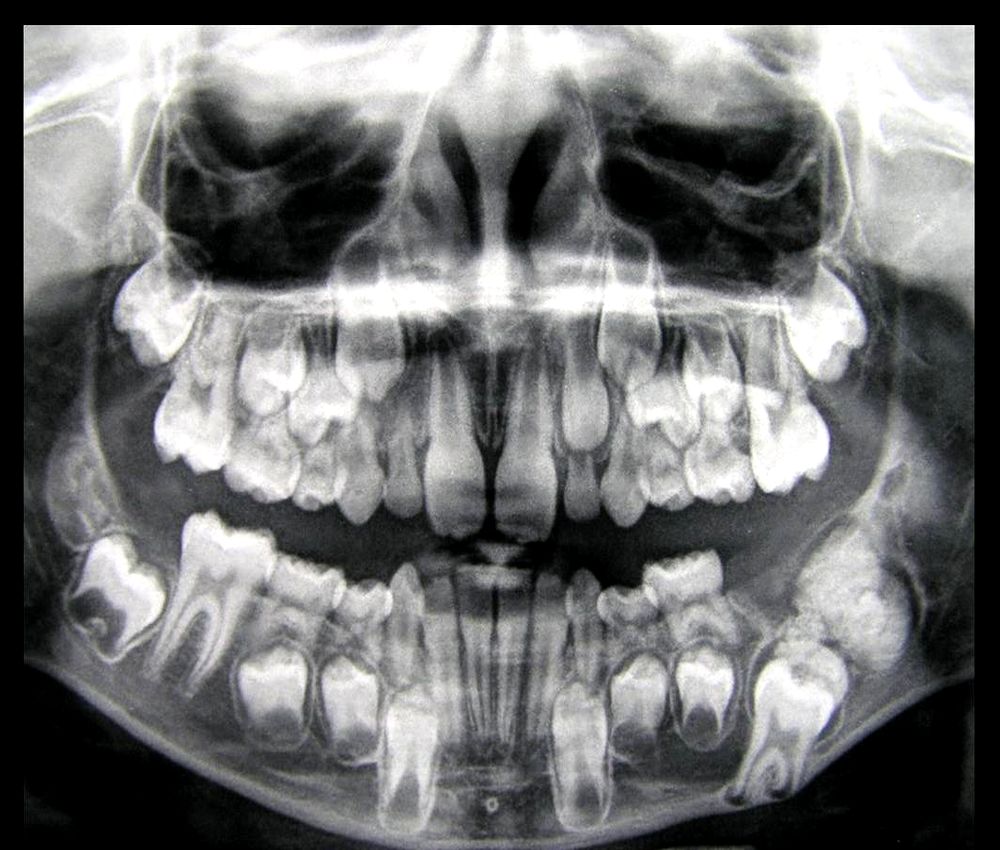

Одонтома нижней челюсти: фотографии и медицинская информация